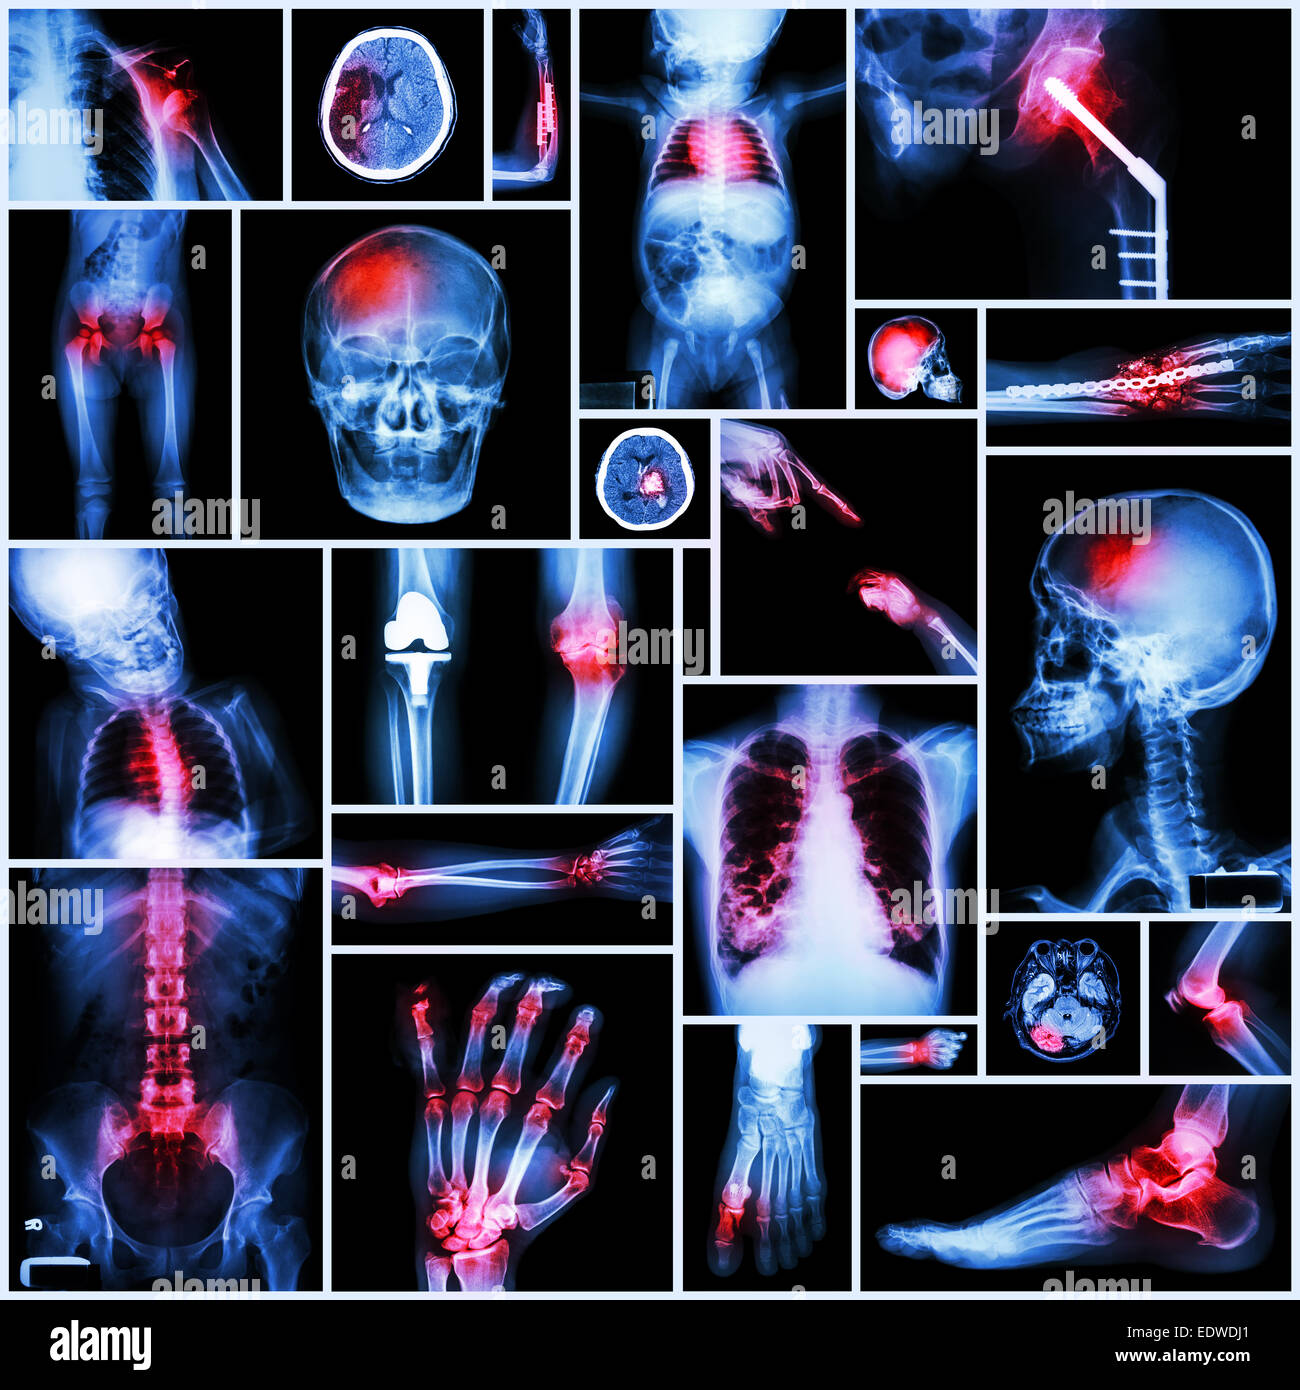

Ensemble de plusieurs rayons-X de la maladie,Plusieurs,chirurgie orthopédique,course,(fracture des os,opération orthopédique,calcul rénal, Banque D'Imageshttps://www.alamyimages.fr/image-license-details/?v=1https://www.alamyimages.fr/photo-image-ensemble-de-plusieurs-rayons-x-de-la-maladie-plusieurs-chirurgie-orthopedique-course-fracture-des-os-operation-orthopedique-calcul-renal-77404872.html

Ensemble de plusieurs rayons-X de la maladie,Plusieurs,chirurgie orthopédique,course,(fracture des os,opération orthopédique,calcul rénal, Banque D'Imageshttps://www.alamyimages.fr/image-license-details/?v=1https://www.alamyimages.fr/photo-image-ensemble-de-plusieurs-rayons-x-de-la-maladie-plusieurs-chirurgie-orthopedique-course-fracture-des-os-operation-orthopedique-calcul-renal-77404872.htmlRFEDX2KM–Ensemble de plusieurs rayons-X de la maladie,Plusieurs,chirurgie orthopédique,course,(fracture des os,opération orthopédique,calcul rénal,

Collection de X-ray plusieurs partie de l'opération orthopédique,et plusieurs maladies (luxation de l'Épaule Fracture,course,de,la goutte, Banque D'Imageshttps://www.alamyimages.fr/image-license-details/?v=1https://www.alamyimages.fr/photo-image-collection-de-x-ray-plusieurs-partie-de-l-operation-orthopedique-et-plusieurs-maladies-luxation-de-l-epaule-fracture-course-de-la-goutte-77391502.html

Collection de X-ray plusieurs partie de l'opération orthopédique,et plusieurs maladies (luxation de l'Épaule Fracture,course,de,la goutte, Banque D'Imageshttps://www.alamyimages.fr/image-license-details/?v=1https://www.alamyimages.fr/photo-image-collection-de-x-ray-plusieurs-partie-de-l-operation-orthopedique-et-plusieurs-maladies-luxation-de-l-epaule-fracture-course-de-la-goutte-77391502.htmlRFEDWDJ6–Collection de X-ray plusieurs partie de l'opération orthopédique,et plusieurs maladies (luxation de l'Épaule Fracture,course,de,la goutte,

Collection de X-ray plusieurs partie de l'opération orthopédique,et plusieurs maladies (luxation de l'Épaule Fracture,course,de,la goutte, Banque D'Imageshttps://www.alamyimages.fr/image-license-details/?v=1https://www.alamyimages.fr/photo-image-collection-de-x-ray-plusieurs-partie-de-l-operation-orthopedique-et-plusieurs-maladies-luxation-de-l-epaule-fracture-course-de-la-goutte-77391497.html

Collection de X-ray plusieurs partie de l'opération orthopédique,et plusieurs maladies (luxation de l'Épaule Fracture,course,de,la goutte, Banque D'Imageshttps://www.alamyimages.fr/image-license-details/?v=1https://www.alamyimages.fr/photo-image-collection-de-x-ray-plusieurs-partie-de-l-operation-orthopedique-et-plusieurs-maladies-luxation-de-l-epaule-fracture-course-de-la-goutte-77391497.htmlRFEDWDJ1–Collection de X-ray plusieurs partie de l'opération orthopédique,et plusieurs maladies (luxation de l'Épaule Fracture,course,de,la goutte,